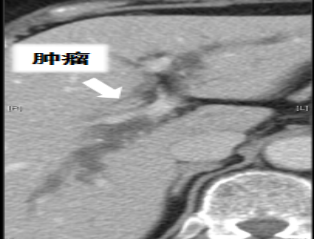

患者病史80岁女性,两周前无明显诱因出现皮肤、巩膜黄染,伴皮肤瘙痒。上腹部CT示肝门部胆管占位伴肝内胆管扩张。2006年因“心绞痛”于外院行“冠脉支架置入术”

病灶评估:通过计算机辅助手术规划系统进行了三维重建,绿色为胆管系统,黄色为肿瘤病灶,红色为主动脉系统。术前诊断:肝门部胆管癌(IV型)

病情特点:病灶主要位于左右肝管汇合部,偏向左侧。患者存在胆管变异,右前、右后肝管不相通,右前胆管汇入左肝管,B4和左外肝管不相通。